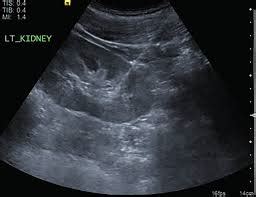

First off, for those who might not be fully familiar, POCUS stands for Point-of-Care Ultrasound. It’s a game-changer in modern medicine, allowing healthcare professionals to perform diagnostic imaging right at the patient’s bedside or in their immediate vicinity. Think about it – getting immediate answers without the patient needing to go to a separate radiology department. This speeds up diagnosis, guides critical decisions, and can significantly improve patient outcomes. POCUS sessions were often organized as training or collaborative events where practitioners could hone their skills, share best practices, and discuss challenging cases. These sessions were invaluable for keeping medical teams up-to-date with the latest advancements and techniques in ultrasound technology and its application. The shutdown of POCUS sessions in 2024 has sent ripples through the medical community, leaving many asking questions about continuity of care, professional development, and the future of POCUS training. The reasons cited often include evolving healthcare regulations, budgetary constraints, shifting institutional priorities, or perhaps even a strategic realignment of resources. Whatever the specific cause, the impact is undeniable. It signifies a pause, or perhaps a fundamental change, in how POCUS skills are disseminated and maintained. This isn’t just about training; it’s about ensuring that medical professionals have the tools and knowledge to provide the best possible care. When these sessions cease, it creates a vacuum that needs to be addressed. We’ll delve deeper into the specifics of why this happened and what it means for the people on the front lines of healthcare.